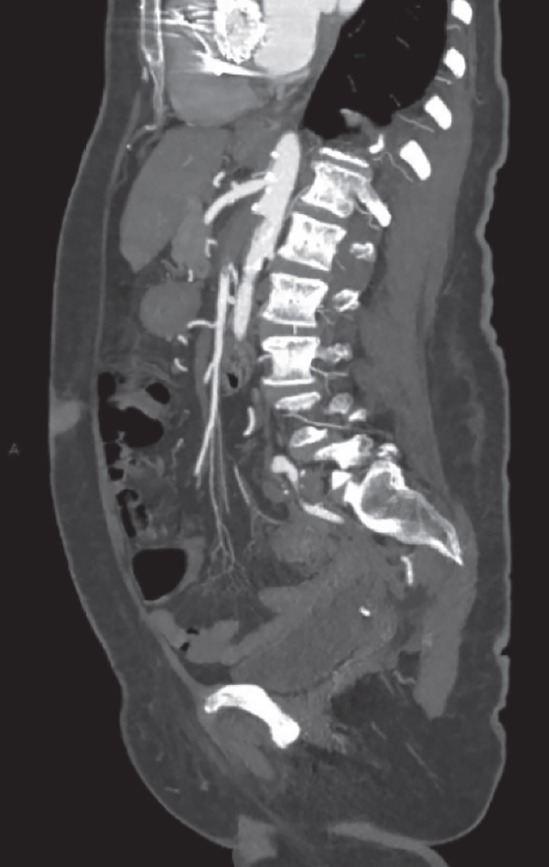

A su ingreso se solicitaron laboratorios generales, los cuales mostraron leucocitosis y anemia normocítica normocrómica grado I de la OMS, el resto de los estudios de laboratorio fueron reportados dentro de los parámetros establecidos por laboratorio; se decidió ingreso hospitalario para abordaje diagnóstico por anemia y gastropatía; se solicitaron estudios de laboratorio de extensión, los cuales reportaron sangre oculta en heces cualitativa positiva y examen general de orina con bacterias escasas. Se inició tratamiento con ceftriaxona y pantoprazol. Al persistir con intenso dolor abdominal, se solicitó tomografía abdominal simple, la cual sugirió trombosis mesentérica, por lo que se realizó complemento con angiotomografía abdominal, que reportó los siguientes resultados: trombosis segmentaria (figura 1) y en la totalidad de la luz de la arteria mesentérica superior con longitud de 37 mm, y posterior recanalización por vascularidad colateral (figura 2), trombosis de la iliaca externa derecha a 9 mm de su nacimiento, que se extiende hasta arteria femoral con opacificación distal (figura 3).

Figura 2 Angiotomografía abdominal, reconstrucción sagital en MIP (máxima intensidad de proyección) que muestra en el nacimiento de la arteria mesentérica superior defecto que ocupa la totalidad de la luz con longitud de 37 mm.